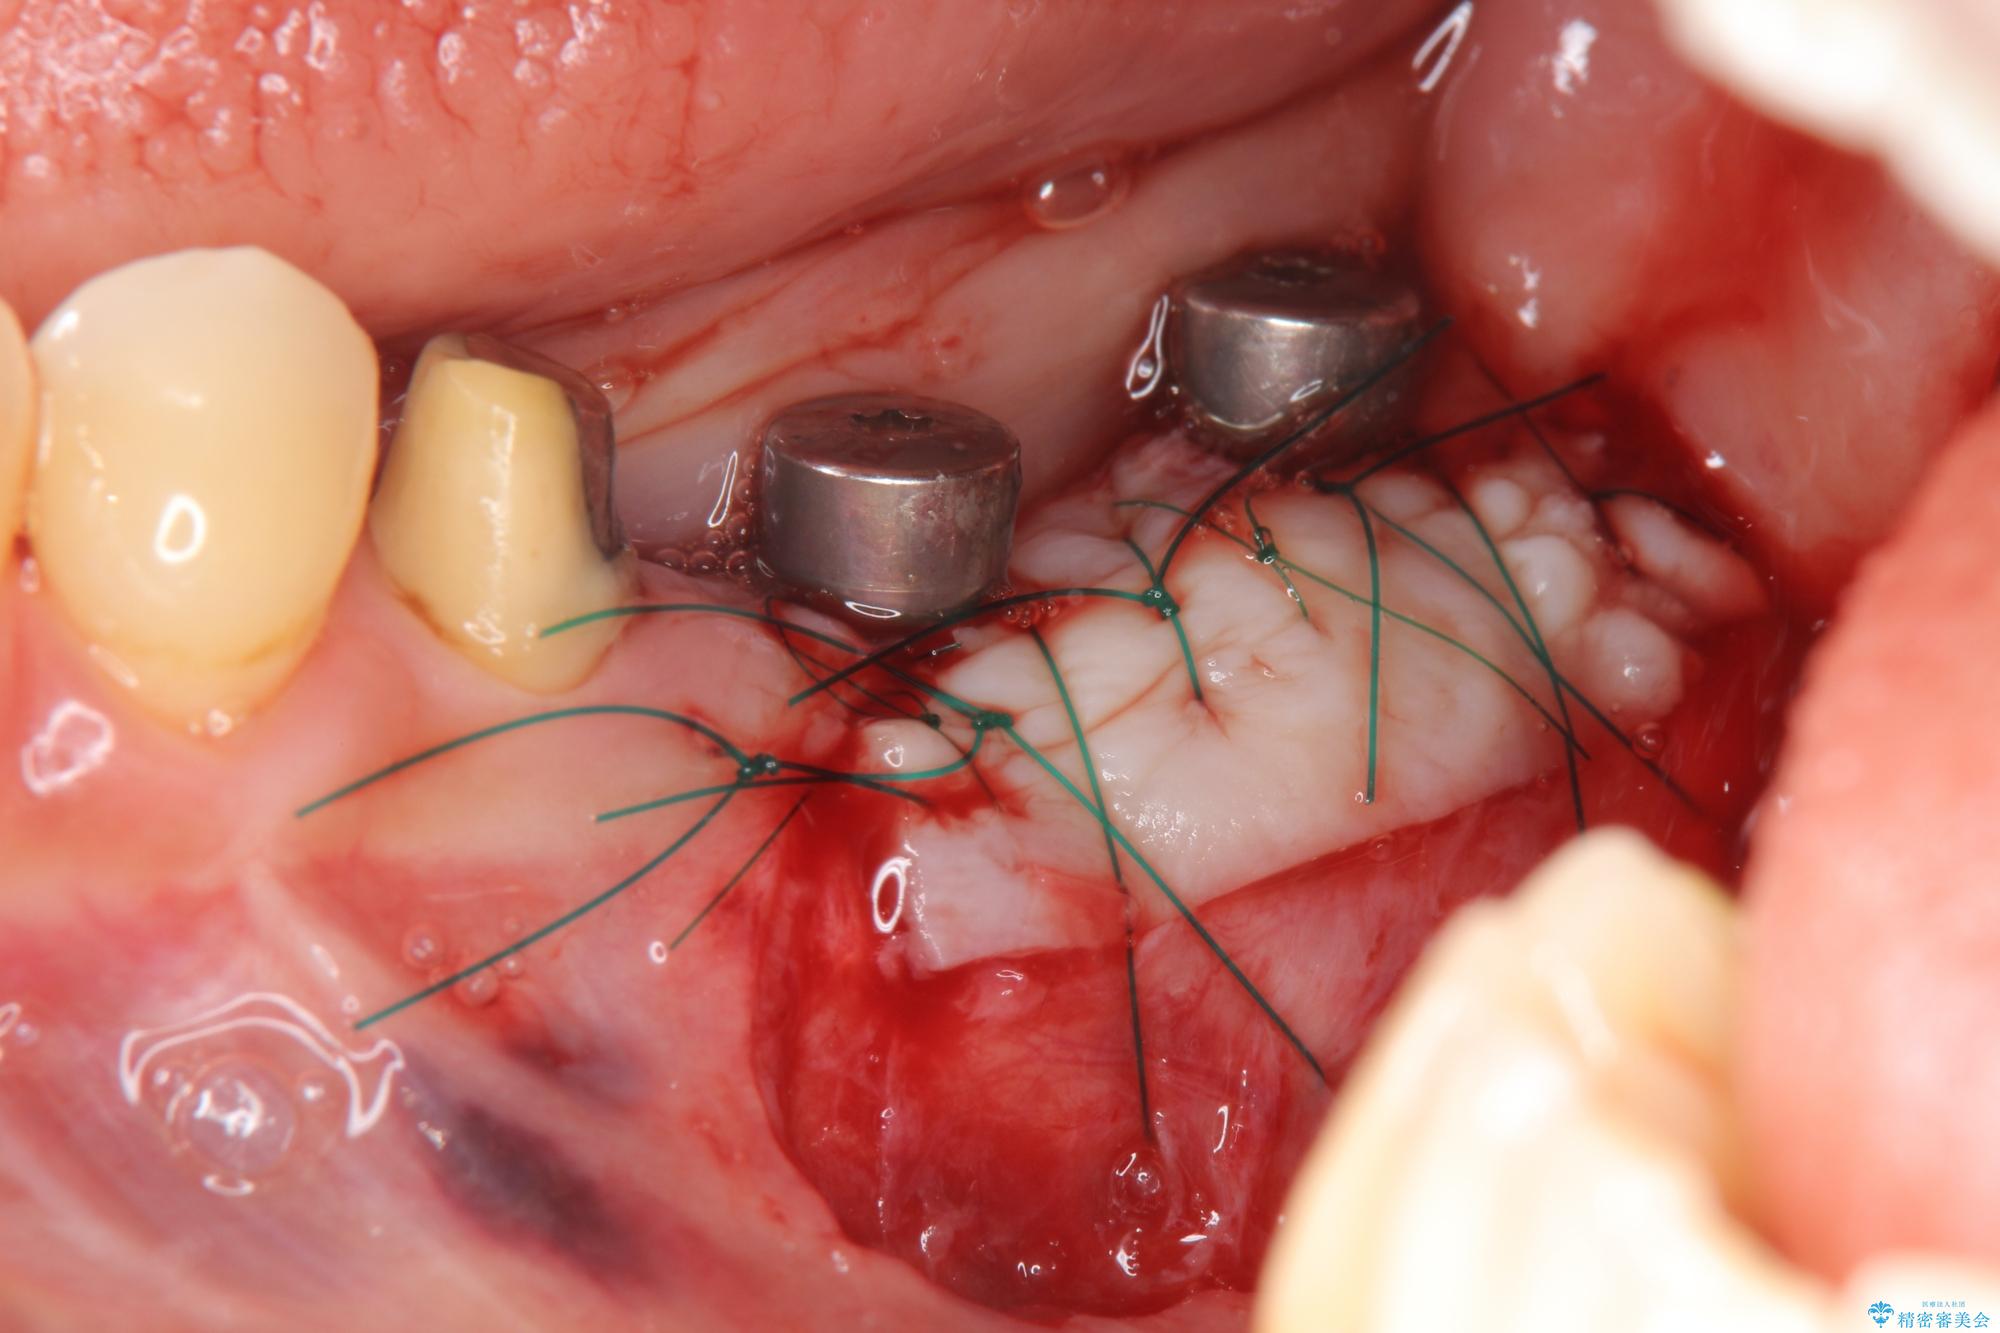

遊離歯肉移植術を併用した、破折歯のインプラント治療

- 他院で根の治療まで終え、違和感が取れず相談に来院されました。

当該歯を精査したところ、歯根に破折が見られ抜歯を余儀なくされました。

抜歯後、インプラントを用いて咬合機能を回復すると共に周囲に強固な角化歯肉を移植することによりより長期にわたり安定したインプラント周囲環境となるよう治療を計画します。

インプラント周囲の角化歯肉が存在することにより、歯ブラシがしやすくなりインプラントにトラブルが起きる確率を減らしより長期的な予後を望むことができます。